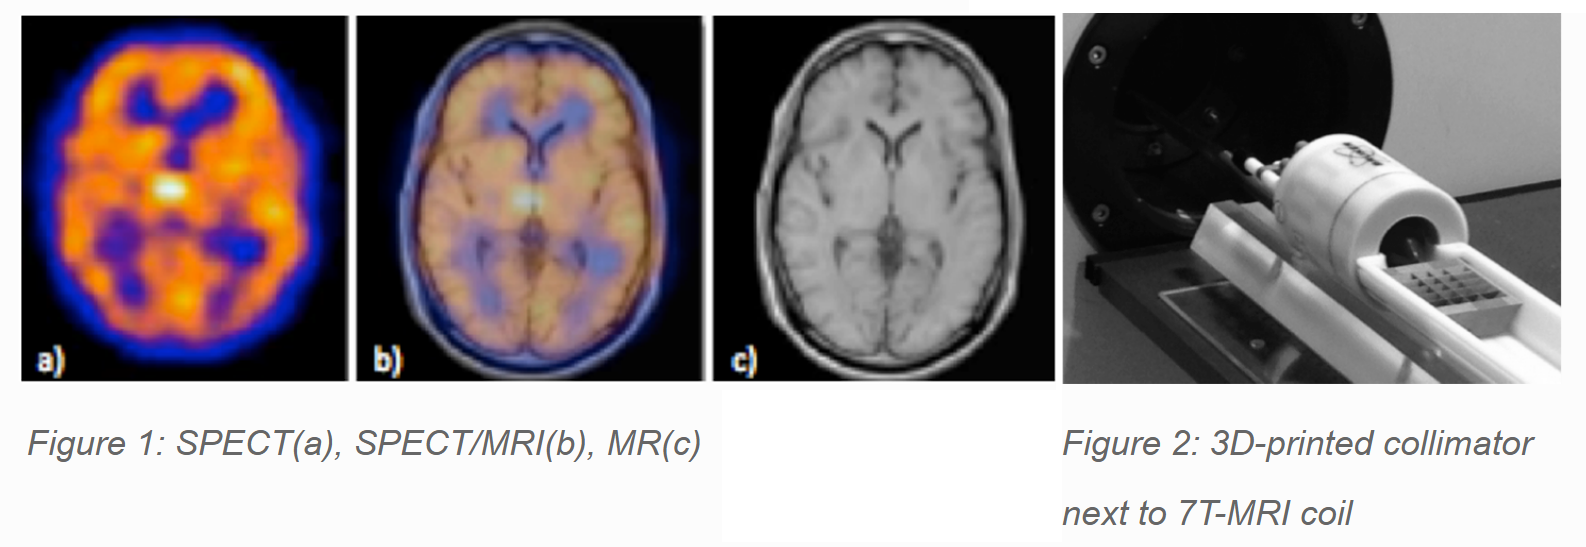

In the last 10 years, there has been a growing interest in multimodality imaging. Integrating different modalities in a single device is advantageous for several reasons: improved patient’s comfort, better diagnosis, and more efficient hospital logistics. Single Photon Emission Tomography (SPECT) and Magnetic Resonance Imaging (MRI) are two complementary modalities: SPECT is a functional imaging technique (Fig. 1a) while MRI is structural (Fig. 1c). A SPECT device consists of two main components: a detector and a collimator. We focus on the MRI-compatibility of SPECT collimators and more specifically 3D-printed tungsten collimators.